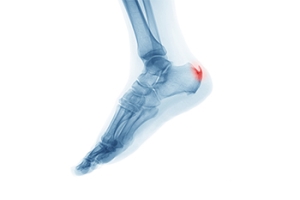

Causes of an Achilles Heel Spur

An Achilles heel spur is a bony growth that develops on the heel bone, typically where the Achilles tendon attaches. It is often the result of repeated stress or strain on the tendon, leading to the formation of extra bone in the area. Common causes include overuse, wearing poor footwear, or activities that put excessive pressure on the heel like running and jumping. Individuals with tight calf muscles or an abnormal gait may also be at higher risk. Symptoms of an Achilles heel spur are pain and tenderness at the back of the heel, particularly when walking, running, or standing for long periods. In some cases, swelling and a visible bump may appear on the heel. If you have developed this type of heel spur, it is suggested that you consult a podiatrist who can accurately diagnose and treat various types of heel spurs.

Heel spurs are formed by calcium deposits on the back of the foot where the heel is. This can also be caused by small fragments of bone breaking off one section of the foot, attaching onto the back of the foot. Heel spurs can also be bone growth on the back of the foot and may grow in the direction of the arch of the foot.

Older individuals usually suffer from heel spurs and pain sometimes intensifies with age. One of the main condition's spurs are related to is plantar fasciitis.

Pain

The pain associated with spurs is often because of weight placed on the feet. When someone is walking, their entire weight is concentrated on the feet. Bone spurs then have the tendency to affect other bones and tissues around the foot. As the pain continues, the feet will become tender and sensitive over time.